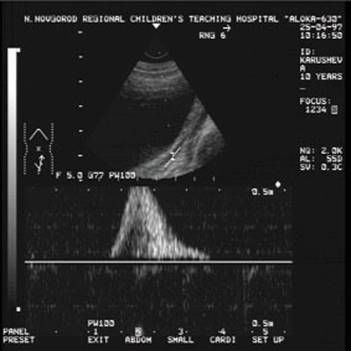

Доплерограма

На малюнку помітно зниження функції нирок виявляється ненасичений інтраренального малюнка, зниження по часу або мінімальної швидкості кровотоку. Всі ці критерії характеризуються патологією і потребують оперативного втручання.

Сканування лівого сечівника через сечовий міхур. На доплерограмах чітко видно криву ретроградногопотіку сечі. Швидкість потіку 0,52m/s, Час 1,16s)

Сканування лівого сечівника через сечовий міхур. На доплерограмах чітко видно криву ретроградногопотіку сечі. Швидкість потіку 0,22m/s, Час 2,38s)

На доплерограмі сечоводів СМР 2,3 і4 ступені спостерігається: делятація сечівника в нижніх і верхніх відділах при середньому або максимальному наповнені сечового міхура, циклічні зиіни діаметра сечівника в нижніх і верхніх відділах: доплерографічна регістрація зворотнього току сечі в сечоводі:стабільне розширення миски: зменшення розмірів нирки.